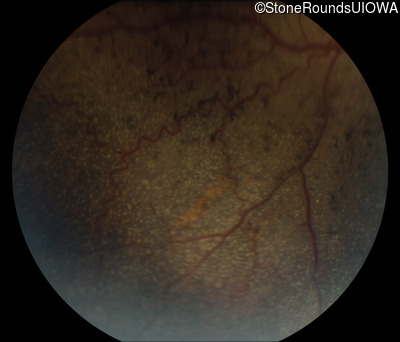

Fundus Photography - Right - 10/300

Exemplar

Fundus Photography - Left - 20/80 -1